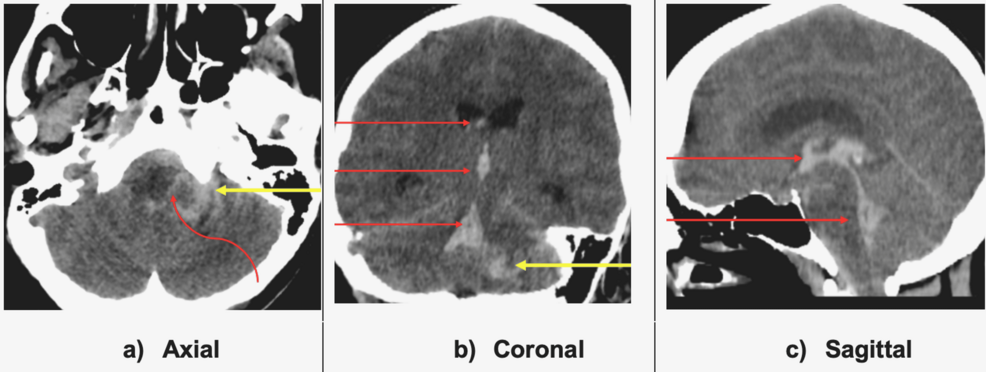

Neuroimaging Findings

• CT head (non‑contrast): Hyperdense collection in the right cerebellar hemisphere extending into the fourth ventricle and lateral ventricles, consistent with cerebellar and intraventricular hemorrhage (IVH). No obvious SAH in basal cisterns.

• CT angiography (CTA): Saccular aneurysm measuring 6 mm arising from the distal PICA near its cortical branches, with contrast extravasation confirming active rupture.

• MRI (T2‑FLAIR, susceptibility‑weighted imaging): Confirmed cerebellar parenchymal bleed, hemosiderin rim around the aneurysm neck, and ventricular blood products.